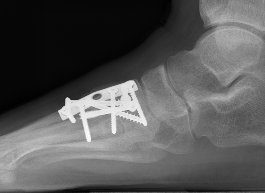

Bridge plate

Advantage

- avoid articular cartilage damage

- avoid broken screws across joint

Bridge plate to 1st TMT and second TMT with Lisfranc screw